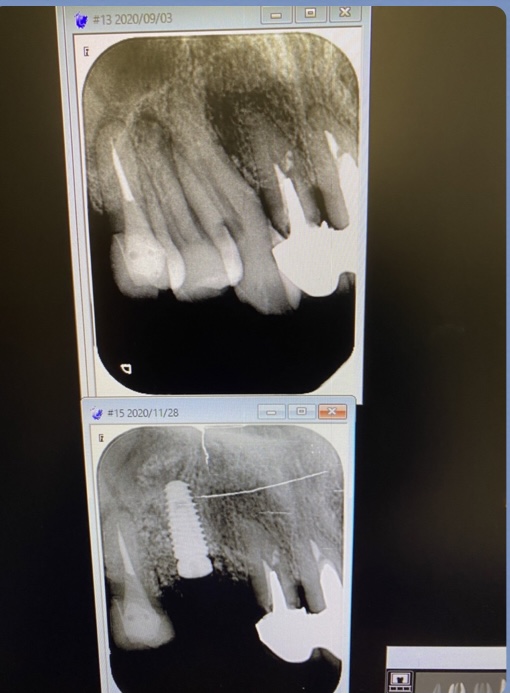

2症例共にソケットリフト法を併用するオペです。

(午前オペ/抜歯即時埋入)

午後の方は、洞底皮質骨に絡み値も良く即時荷重非接触の仮歯まで装着しました。